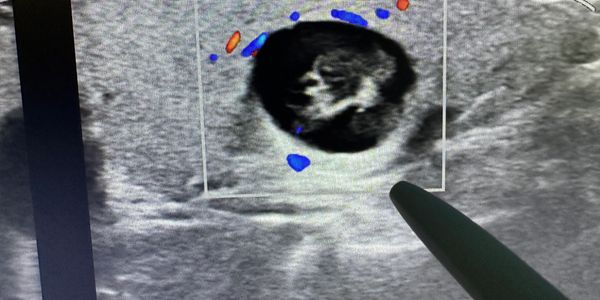

Dr. John Sabra is board certified by the American Board of Surgery and is a Fellow of the American College of Surgeons. He has more than 20 years of focused experience in the surgical evaluation and treatment of thyroid and parathyroid diseases. Trained at UT Southwestern–Parkland Memorial Hospital, he provides comprehensive, patient-centered care ranging from in-office ultrasound and biopsy to advanced minimally invasive and surgical treatments.

Dr. Sabra is widely recognized for his expertise in thyroid nodule management and is among the earliest adopters of radiofrequency ablation (RFA) in Texas, offering effective non-surgical options for appropriately selected patients. His practice is built around individualized treatment plans, careful decision-making, and excellent outcomes.